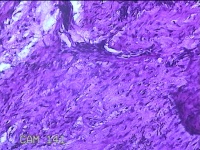

左侧膝部皮下结节

性别

男

年龄

7岁

临床诊断

皮下结节

一般病史

发现左侧膝部皮下结节2年余,无明显疼痛及不适。

标本名称

大体所见

灰白暗红色组织1.5x0.8x0.7cm一块,表面带梭形皮肤1.5x0.8cm,皮下见结节1.5x0.8x0.3cm一个,切开结节呈囊性,囊内有少许清亮液体,囊壁厚0.1cm。